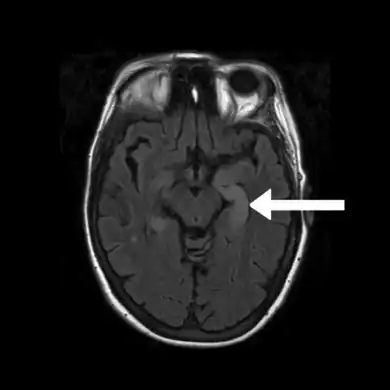

Image of limbic encephalitis (and positive NMDAR antibodies in the CSF)- increased signal intensity is seen in the bilateral medial temporal lobes and hippocampi.

FLAIR MRI-Indicates bright signal from medial temporal lobe consistent with limbic encephalitis arrow

Neuroimaging

Brain MRI is the mainstay of initial investigation pointing to limbic lobe pathology revealing increased T2 signal involving one or both temporal lobes in most cases.[22][14]

Serial MRI in LE starts as an acute disease with uni- or bilateral swollen temporomesial structures that are hyperintense on fluid attenuation inversion recovery and T2-weighted sequences. Swelling and hyperintensity may persist over months to years, but in most cases progressive temporomesial atrophy develops.[23]